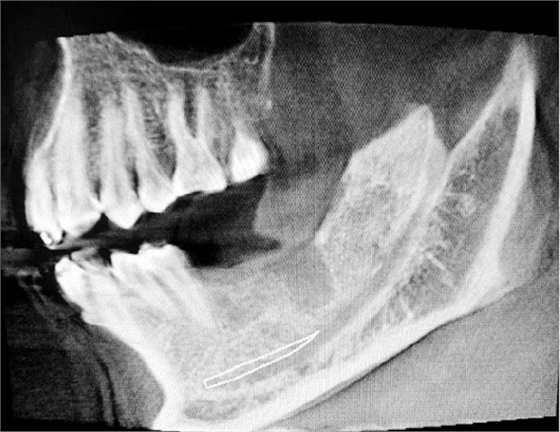

左下67缺失

美康口腔王主任手術過程中

種入植體

術后拍片